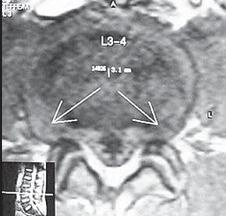

На МРТ № 15 наблюдается двухсторонняя экстрафораминальная грыжа межпозвонкового диска (расположенная за межпозвонковыми отверстиями) На МРТ № 16 наблюдается медиолатеральная протрузия и вентральная грыжа межпозвонкового диска